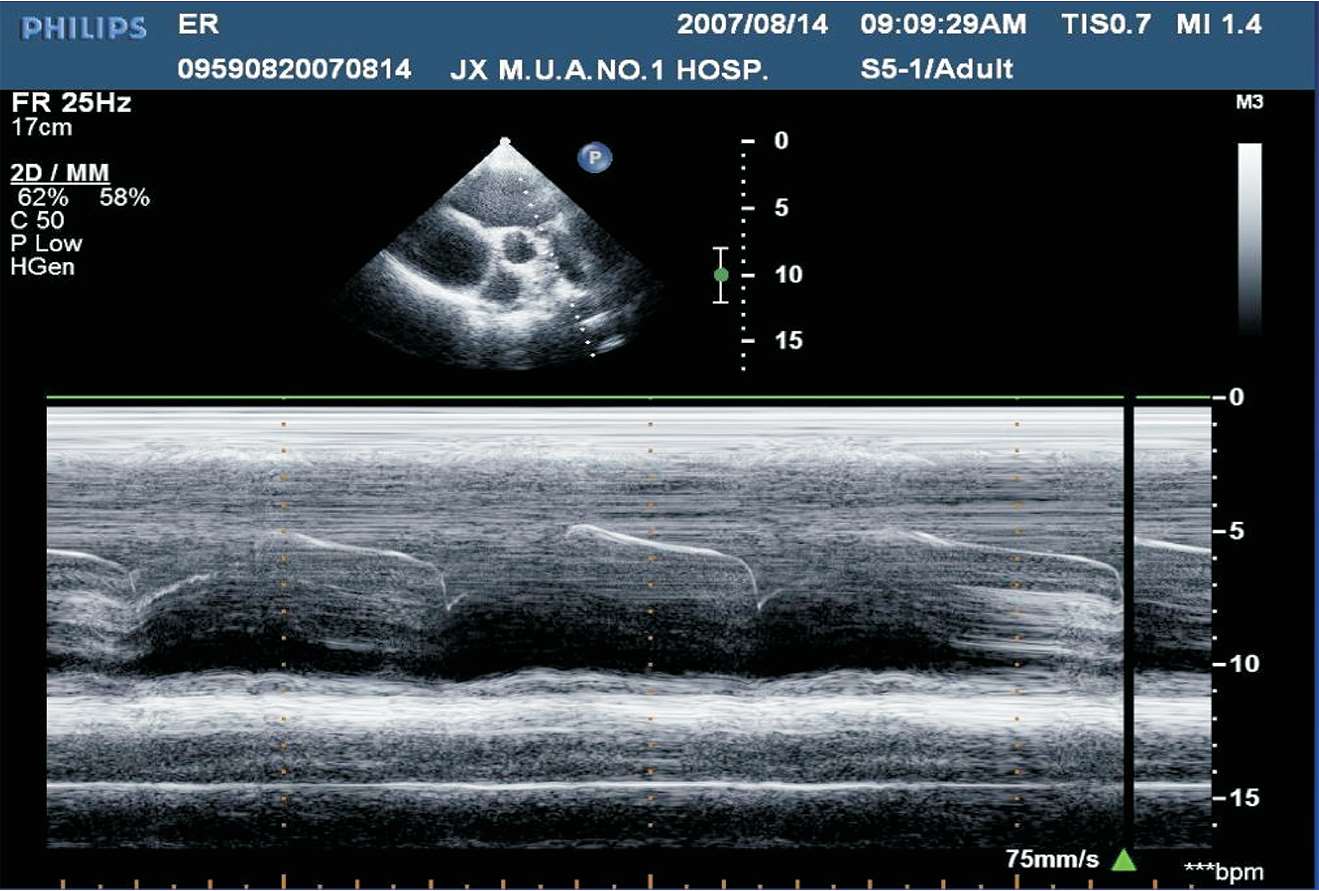

(1)M型超声心动图,适用于左心室无节段性运动异常者。取标准胸骨旁左心室长轴切面,取样线置于二尖瓣腱索水平,测量左心室舒张末期内径(LVD)与收缩末期内径(LVS),根据测量内径推算左心室舒张末期及收缩末期的容量,再根据左心室舒张末期容量及收缩末期容量的变化求出心输出量(见图1-36)。

图1-36 左心室波群